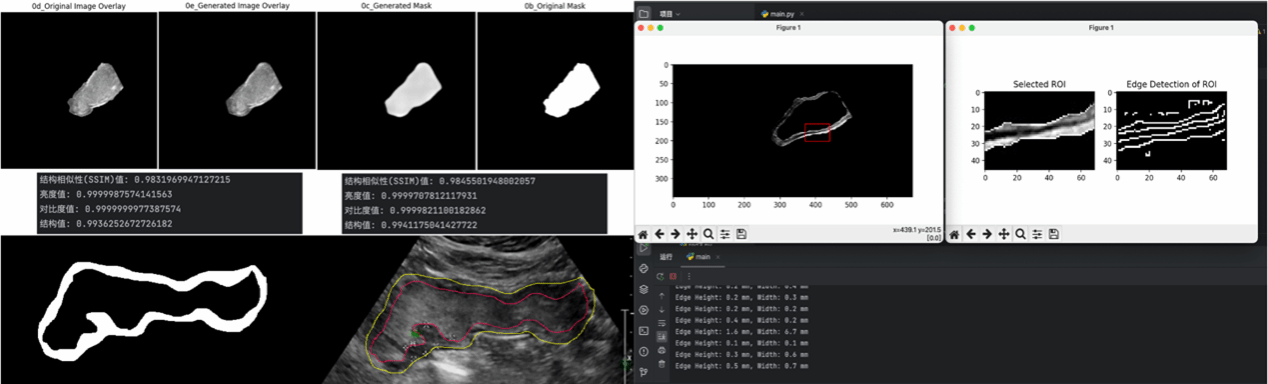

“智能胃超声”项目组由我院学生本科生丁铭泽、张鑫彦和殷莉钦组成,由我院刘斌教授担任项目组的指导教师。项目组与中国医科大学附属盛京医院刘治军教授团队合作,围绕经腹胃超声及胃癌多模态影像,通过项目组自主探索的“UC-Net”神经网络模型,实现胃部超声区域的智能定位与胃壁厚度的自动测量。

项目组在世界卫生组织常规胃癌分型基础上,引入亚洲胃癌分型方案。旨在提高胃超声在常规胃病筛查的使用比例与早期胃癌的检出率,改善患者胃部检查舒适度,力争为胃部超声检查专业人才的培养以及亚洲人群胃部疾病患者的诊治提供助力。